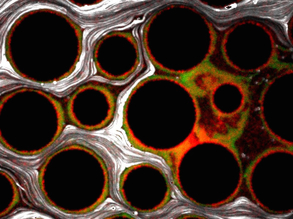

Tough Stuff